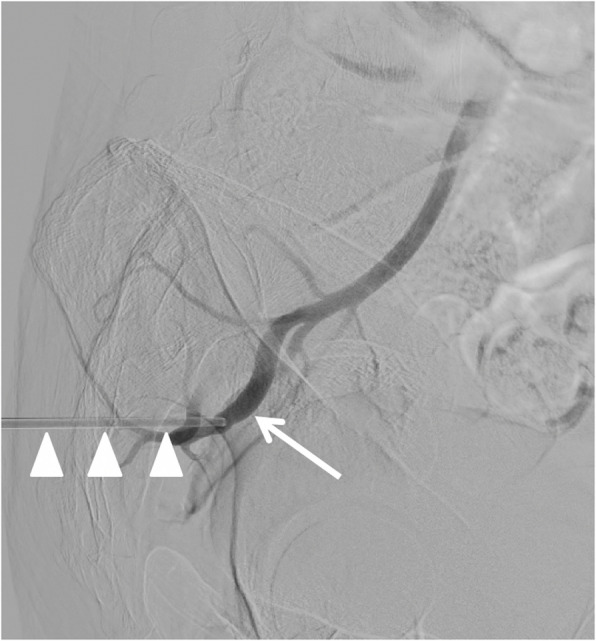

Background: Iatrogenic superior gluteal artery injury (SGA) following bone marrow biopsy is rare but potentially life-threatening. Due to the deep intrapelvic location of the vessel, conventional management with manual compression or surgical repair is challenging. Traditional management via endovascular coil embolization requires arterial access and vessel sacrifice. Case presentation We present a case of SGA injury resulting from a bone marrow biopsy in a patient with suspected T-cell lymphoma. The injury was successfully managed using a 6 french Angioseal closure device applied directly through the biopsy puncture site in the gluteal region, with the patient maintained in the lateral decubitus position. The approach achieved immediate hemostasis while preserving arterial patency.

Conclusion: This represents the first reported use of an Angioseal device for direct percutaneous treatment of iatrogenic SGA injury. This technique offers an effective hemostasis and vessel preservation, expanding the interventional radiology's armamentarium.